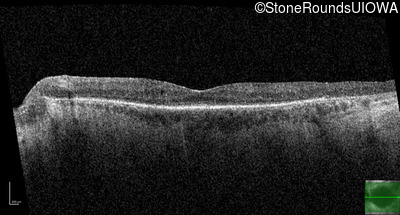

Optical Coherence Tomography - Left - 20/40 -1

Exemplar / OCT Stack

OCT Stack